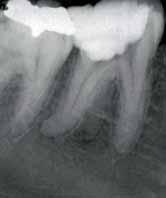

A 40-year-old male patient presented with a complaint of pain in the posterior right mandibular region for two weeks. He gave a history of intermittent pain in the same region for the past two months. His past medical history was found to be non-contributory, clinical exam revealed a carious right mandibular first molar. The clinical and radiographic findings led to a diagnosis of chronic

irreversible pulpitis of the right mandibular first molar which requires endodontic therapy.

Radiographic evaluation of the involved tooth indicated a normal canal configurations of canals. (Figure 1)

Endodontic access was carried out under local anesthesia and rubber dam isolation. Four canals were detected following access preparation, two each in distal and mesial root. After debridement of the pulp chamber, some pulp tissue remained at the isthmus of mesial orifices. Further, careful probing in the isthmus area with an endodontic explorer revealed an intermediate canal. (Figure 2). Distal angulation working length radiograph showed three distinct canals mesially and two canals distally joiningat the apex. (Figure 3). All the five canals were negotiated and working length was determined. Cleaning and shaping was performed using crown down preparation with Profile nickel titanium rotary instrument (Maillefer, Dentsply), along with copiousirrigation of sodium hypochlorite and RC Prep (Premier,USA). On the second visit, master cone selection was made and obturated by lateral condensation procedure. The patient was recalled for check up and after a week, the tooth was restored with a permanent restoration. (Figure 4). The patient was followed up for two years.

Figure 1- Pre operative radiograph showing distal caries. Figure 2- Pulp chamber floor showing three independant mesial and two distal orifices. Figure 5- Pre operative radiograph showing mesial root and a distal root with an additional indistinct distolingual root. Figure 6- Pulp chamber showing three mesial and two distal canal orifices. Figure 7- Working length radiograph taken with distal shift technique. Figure 8- Post operative obturation radiograph showing three mesial and two separate distal roots. Figure 3 - Working length radiograph reveals three canals in the mesial root and two canals in the distal root. Figure 4- Post operative obturation radiograph.